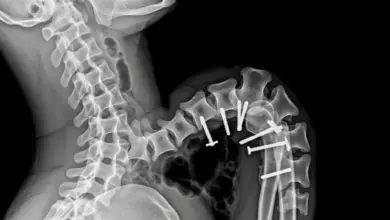

Em casos de curvaturas mais severas ou de escoliose progressiva, a cirurgia pode ser considerada, com o objetivo de nivelar a coluna e, com isso, proporcionar uma estrutura mais estável e uma redução significativa dos sintomas.

No entanto, a decisão por essa alternativa deve ser ponderada diante de uma análise detalhada de prós e contras, dependendo do quadro clínico individual.